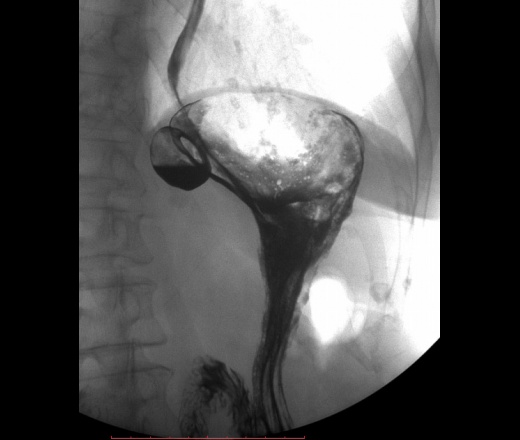

Локализация харатерная для дивертикула желудка(задняя стенка свода), тип дивертикула нехарактерный по механизму формирования, тут по типу пульсионного, характерен тракционный механизм, за счёт явлений перипроцесса. Может быть я и неправ.

"Дивертикулы желудка Дивертикулы желудка (ДЖ) встречаются очень редко, случайно они обнаруживаются в 0,02% случаев аутопсий [57]. ДЖ имеют грушевидную, реже – овальную форму, размеры их обычно небольшие, слизистая оболочка чаще не изменена. Юкстакардиальные ДЖ составляют до 75% всех ДЖ. Они наиболее часто локализуются в области пищеводно-желудочного соединения, обычно на малой кривизне желудка, чаще на задней стенке, что объясняют особенностью расположения мышечных пучков собственного мышечного слоя стенки желудка. ДЖ наиболее часто встречаются в среднем возрасте и имеют размеры от 1 до 3 см в диаметре [58, 59]. Интрамуральные или частичные ДЖ формируются путем выпячивания слизистой оболочки через мышечный слой. Такие ДЖ чаще встречаются в препилорической зоне, обычно в области большой кривизны желудка [60]. При проведении эндоскопии или бариевого контрастирования стриктуры пептические язвы и другие деформации могут иметь сходство с препилорическими ДЖ."http://helpiks.org/3-80531.html

Дивертикулы желудка (ДЖ) встречаются очень редко, случайно они обнаруживаются в 0,02% случаев аутопсий [57]. ДЖ имеют грушевидную, реже – овальную форму, размеры их обычно небольшие, слизистая оболочка чаще не изменена.

Юкстакардиальные ДЖ составляют до 75% всех ДЖ. Они наиболее часто локализуются в области пищеводно-желудочного соединения, обычно на малой кривизне желудка, чаще на задней стенке, что объясняют особенностью расположения мышечных пучков собственного мышечного слоя стенки желудка. ДЖ наиболее часто встречаются в среднем возрасте и имеют размеры от 1 до 3 см в диаметре [58, 59]. Интрамуральные или частичные ДЖ формируются путем выпячивания слизистой оболочки через мышечный слой. Такие ДЖ чаще встречаются в препилорической зоне, обычно в области большой кривизны желудка [60]. При проведении эндоскопии или бариевого контрастирования стриктуры пептические язвы и другие деформации могут иметь сходство с препилорическими ДЖ."http://helpiks.org/3-80531.html